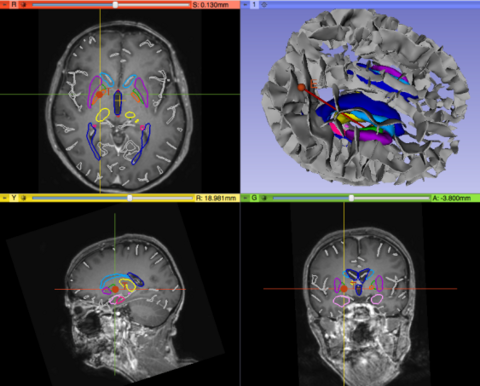

• Upgrade of the PyDBS modules for Parkinson Surgery to Slicer4.4